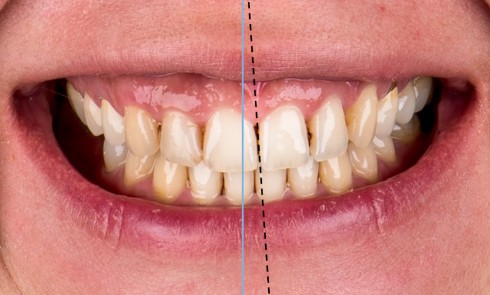

Toute réhabilitation du secteur antérieur doit répondre à des objectifs mécaniques, biologiques, fonctionnels et esthétiques [1]. Obtenir un résultat naturel...Le rôle de l’assistant(e) lors de l’éclaircissement dentaire